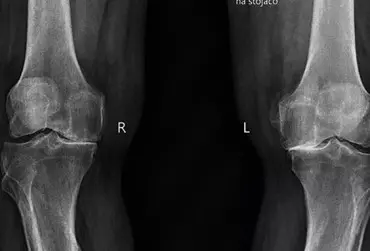

Endoprotezoplastyka stawu kolanowego — kompleksowa fizjoterapia szpitalna

Zwiększona aktywność fizyczna zarówno amatorska, jak i zawodowa może powodować wiele urazów, które w perspektywie czasu przyczyniają się do powstania rozmaitych chorób. Przeważnie choroba zwyrodnieniowa stawów przyczynia się do zmniejszenia ruchomości stawowej skutkującej różnorodnymi niedogodnościami. Schorzenie to stanowi również poważny problem nie tylko medyczny, ale również ekonomiczny. Zważywszy na fakt, iż jesteśmy społeczeństwem starzejącym się, z pewnością problem z roku na rok będzie się pogłębiał.

Zastosowanie niskich temperatur w leczeniu urazów więzadłowych stawu kolanowego

Podczas aktywności fizycznej jesteśmy narażeni na różnego rodzaju urazy prowadzące w dużej mierze do zaburzeń wzorców ruchowych. Taki stan może prowadzić do wystąpienia wielu chorób, które bezpośrednio lub pośrednio negatywnie wpływają na pracę poszczególnych układów. Zwłaszcza układ ruchu jest wrażliwy na niewłaściwą pracę np. stawu biodrowego lub stawu kolanowego. Uszkodzenie aparatu więzadłowego stawu kolanowego prowadzi do zaburzenia stabilności kończyny dolnej i niewłaściwej pracy okolicznych stawów. Takie patologiczne postępowanie predysponuje do szybszego zużycia się określonych struktur wewnątrzstawowych.